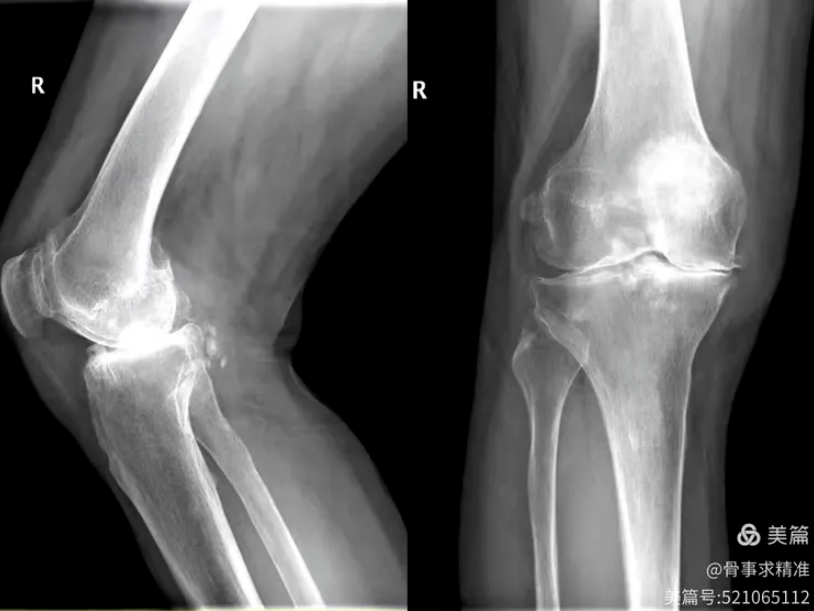

机器人系统在辅助全膝关节置换中,通过术前三维重建与个体化规划,实现不开髓、数据化精准截骨,最大限度保留骨量,创伤更小、出血更少、疼痛更轻、恢复更快。术中假体位置、角度、旋转对位全程精准控制,大幅度降低人为误差,提升手术安全性。

膝关节术前片